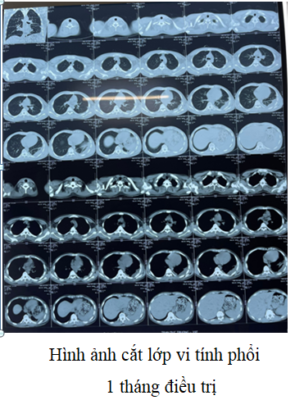

Bệnh nhân nam, 19 tuổi, tiền sử khỏe mạnh. Cách nhập viện 8 ngày biểu hiện mệt mỏi, ho, sốt, đau tức ngực trái. Nhập viện vào khoa Hồi sức cấp cứu, Bệnh viện Quân y 17 trong tình trạng rất nặng với triệu chứng mệt nhiều, sốt cao, khó thở, suy hô hấp. Khoa Hồi sức cấp cứu đã tiến hành cấp cứu kịp thời, thực hiện đặt nội khí quản, thở máy, nội soi khí phế quản để tầm soát tổn thương, lấy mẫu bệnh phẩm cấy khuẩn và làm kháng sinh đồ. Kết quả xét nghiệm máu cho thấy tình trạng nhiễm trùng máu rất nặng. Kháng sinh phổ rộng được sử dụng ngay lập tức theo kinh nghiệm. Kết quả chụp cắt lớp vi tính phổi trái bị xẹp hoàn toàn, có nhiều đám tổn thương đông đặc và tràn dịch màng phổi mức độ nhiều. Ngay khi có kết quả cấy đờm là vi khuẩn Burkholderia pseudomallei và kháng sinh đồ nhạy cảm với một số kháng sinh. Bệnh nhân được điều trị ngay theo kháng sinh đồ và đáp ứng tốt với kháng sinh. Bệnh diễn biến khá hơn, hết sốt, tuy nhiên vẫn còn đau ngực trái nhiều, khó thở. Chụp lại cắt lớp vi tính lồng ngực phổi trái vẫn còn tổn thương nặng. Bệnh viện Quân y 17 đã hội chẩn với Bệnh viện 175, Bệnh viện Đà Nẵng thống nhất phẫu thuật mở ngực bóc vỏ phổi, làm sạch màng phổi, cắt lọc tổ chức phổi hoại tử, dẫn lưu khoang màng phổi, tiếp tục điều trị phối hợp thuốc, đồng thời tăng cường nuôi dưỡng tích cực, cân bằng nước điện giải, khoáng chất, tập phục hồi chức năng hô hấp. Sau 1 tháng điều trị, bệnh nhân phục hồi, toàn trạng ổn định, chuyển khoa khác tiếp tục điều trị duy trì